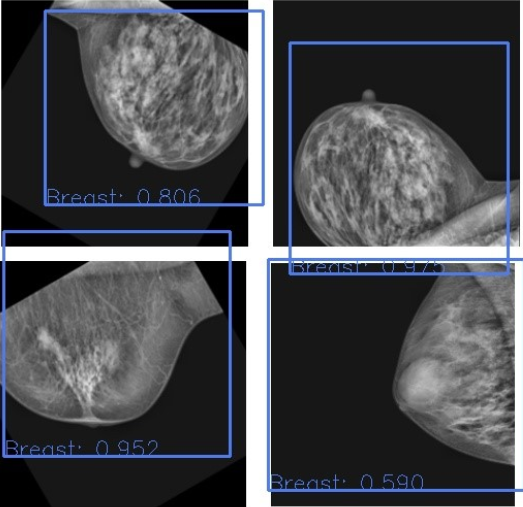

project-1

Mammography Classification